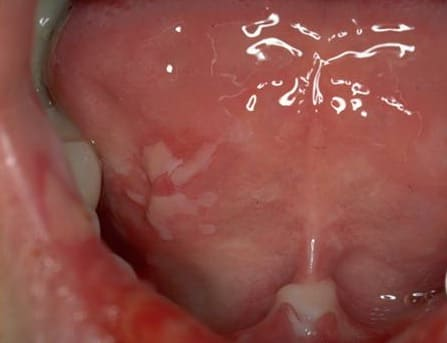

Pemphigis Vulgaris =الفقاع الشائع